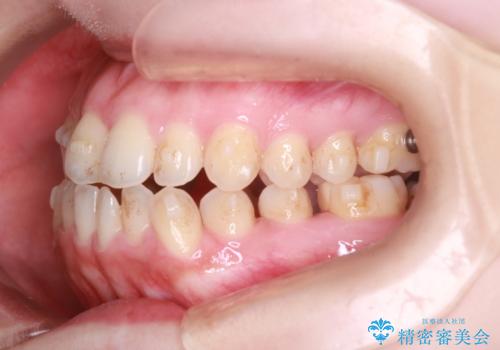

【オープンバイト】前歯のがたがたをなおしたい。

- 笑った時の前歯の見た目が気になることを主訴に来院されました。

上の歯が下の前歯を少し隠すぐらいを目指し、インビザラインにて治療を行いました。